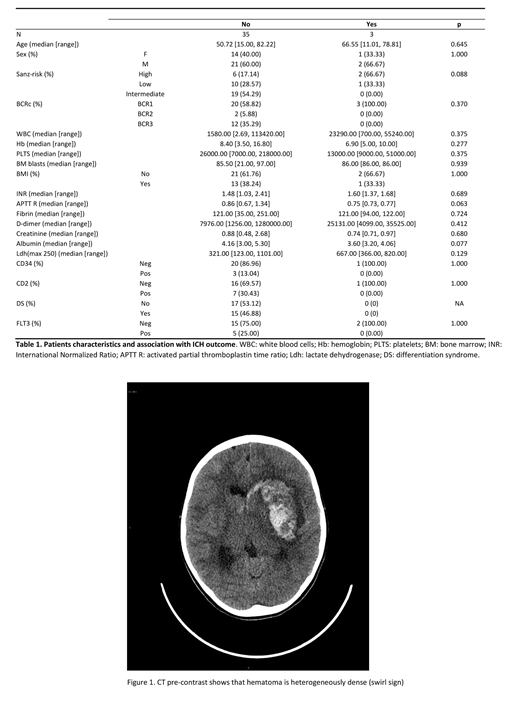

We retrospectively identified 38 patients with APL (23 males and 15 females with a median age of 51.83 years, range 11-82), consecutively diagnosed at our Institution between 2004 and 2019, and treated with standard ATRA-based induction (Table 1). Occurrence of ED and ICH was then correlated with clinico-biological parameters, selecting for commonly reported variables predictors of these complications. In addition, CT scans of the 5 patients who experienced an intracranial hemorrhage (ICH) were revised by an expert neuroradiologist, looking for radiographic predictors of poor outcome (Al-Mufti et al 2018).

Approximately 13% (5/38) of our APL patients experienced an ICH during induction therapy, which was fatal in 3 cases, while the overall incidence of ED was about 10% (4/38, including 1 case of death due to a differentiation syndrome). Looking at clinico-biological variables, the only predictor of ICH was a lower albumin level at baseline (3.8 vs 4.2 gr/dl; p=0.022), as compared to patients who did not experience ICH. A high Sanz-risk score was present in 2 of 3 pts with a fatal outcome of ICH (67% of cases), together with a shorter activated partial thromboplastin time (aPTT, 0.75 vs 0.86 ratio)(Table 1). Looking at neuroradiological findings (Figure 1) the three fatal cases showed a wider ICH volume, with perilesional edema and, interestingly, a positive "swirl" sign, which is defined as a marker of ongoing extravasation of blood within a hematoma. Both cases with a favourable outcome had a cerebellar involvement, without perilesional edema, and no major involvement of basal ganglia or thalamus. None of the patients had radiological signs of arteriovenous malformations.

Our data remark the impact of lower albumin levels at baseline and of a high Sanz-risk category on ED in patients with APL. In APL cases with fatal ICH, the thrombo-hemorrhagic imbalance is more profound than in other AMLs and results in a more devastating clinical picture. Taking into account the limitations of the small sample size, we found that a wide hemorrhage volume with perilesional edema, and the presence of the "swirl" sign are characteristic of fatal cases, while arteriovenous malformations did not seem to play a predisposing role. Further studies including large series of patients are warranted to identify the characteristics and the possible strategies to ameliorate the outcome of ICH in APL.